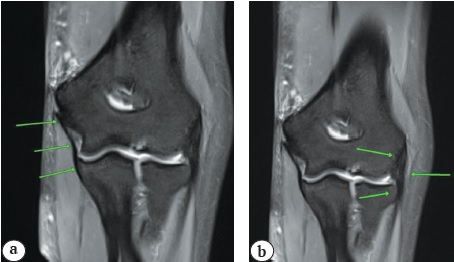

На томограммах в коронарной проекции изучали особенности топографии и морфометрические характеристики капсульно-связочных структур ЛС, а именно лучевой коллатеральной связки (ЛКС) и переднего пучка медиальной коллатеральной связки (ППМКС) (рис. 6). На томограммах в сагиттальной проекции изучались размеры зон прикрепления сухожилий КЛРЗ и ЛСЗ к латеральному и медиальному надмыщелкам плечевой кости.

Рис. 6. МРТ локтевого сустава, аксиальная проекция. Стрелками обозначены: а — передний пучок локтевой коллатеральной связки; b — лучевая коллатеральная связка

В заключительной части клинического исследования определяли длину медиальной и лучевой коллатеральных связок, а также площадь зон их прикрепления. По данным МРТ, средняя длина ППМКС составляет 20,5 (19,6–23,5) мм. Лучше всего на МРТ он визуализируется на фронтальных срезах. Средняя длина ЛКС составляет 26,5 (24,7– 28,7) мм. Выявленные показатели могут быть полезны в случаях их ятрогенного повреждения при выполнении релиза поврежденных сухожилий.